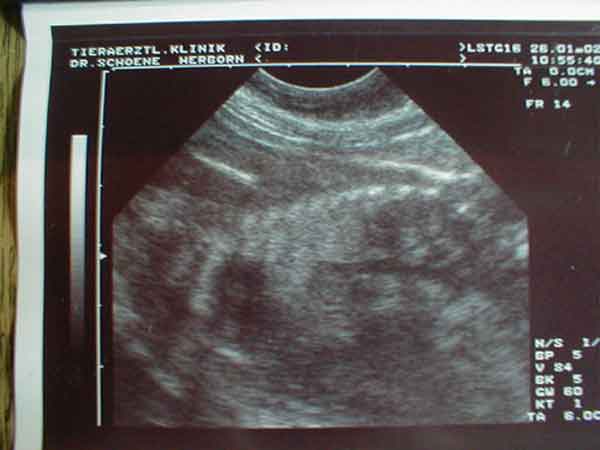

Während des Ultraschalls vom 26.01.2002 am Tag 55 nach Decktermin konnte man deutlich den Herzschlag eines Welpen erkennen. Hier das Foto:

Man erkennt im linken mittigen Bereich das Herz(schwarzer Fleck) eines Welpen sowie seine Wirbelsäule(hell, geschwungen).